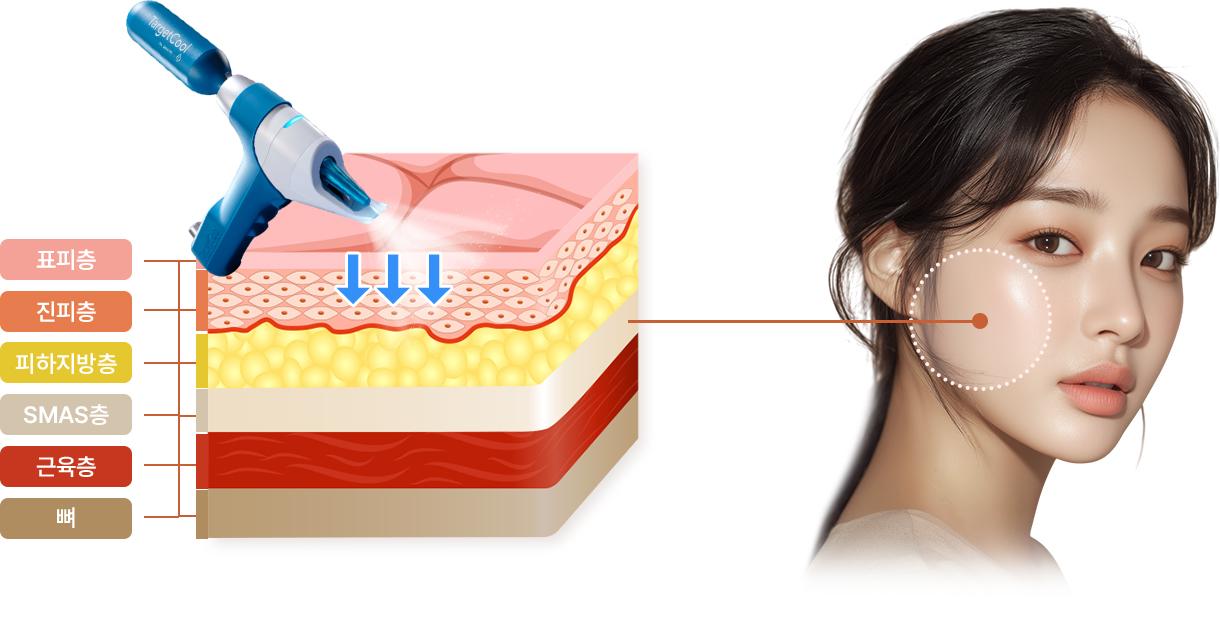

Chill하게~ 비침습 냉각 마취로

통증은 줄이고, 탄력은 높이다!

STEP 1

-10℃~-5℃ 냉각기술로

-10℃~-5℃ 냉각기술로

시술전 통증 최소화

STEP 3

피부속까지 바꾸는 탄력 & 광채효과

아이스 니들링으로 진피층까지 스킨부스터 앰플투입